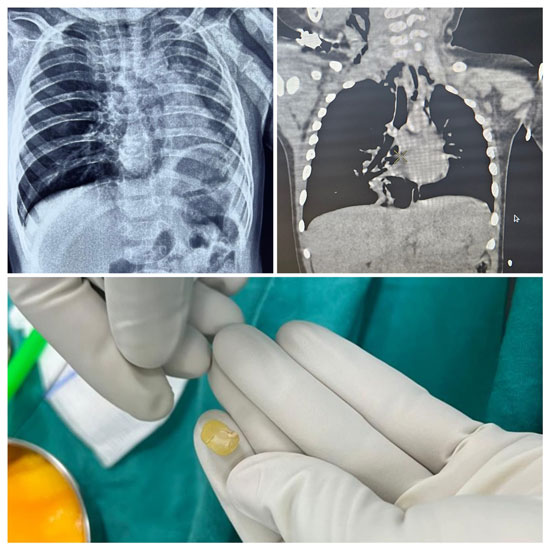

Upon arrival at KMC Hospital, the child was assessed by Dr Swathi Rao, consultant - paediatric intensivist, who immediately recognized the seriousness of the condition. Despite initial hesitation from the family, the child’s respiratory status worsened, with oxygen saturation falling to 88 percent and visible distress. An urgent CT scan of the thorax confirmed a foreign body obstructing the right bronchus, resulting in hyperinflation of the right lung and compression of the left lung and heart.

An expert opinion was promptly obtained from Dr Gautham Kulamarva, consultant ENT surgeon. Despite it being Christmas Eve night, seamless coordination was achieved between the ENT team, operating room staff, the anaesthetist team led by Dr Sunil and Dr Frieda, and the administration teams of KMC Hospital at both Ambedkar Circle and Attavar, enabling all logistics to be arranged swiftly. The child was immediately taken to the operating room at midnight, where Dr Kulamarva performed an emergency bronchoscopic removal, safely retrieving the foreign body obstructing the right bronchus without complications. As nearly 18 hours had elapsed since the incident and early signs of waterlogging had developed in the lungs beyond the obstruction, the child was electively ventilated for a few hours and successfully extubated after six hours.